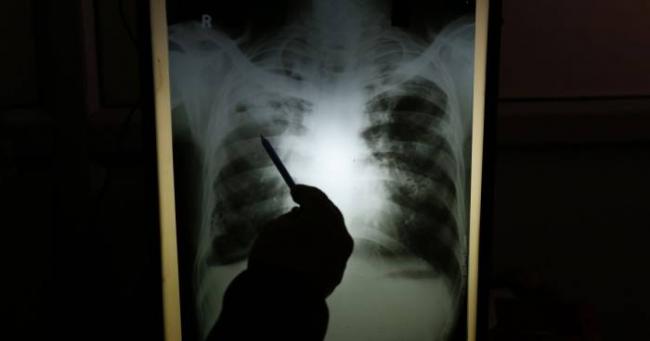

- рентгенография органов грудной клетки;

Незаменимым для постановки точного диагноза пневмонии является рентгенография грудной клетки. Она проводится в прямой, а при необходимости и в боковой проекции и позволяет не только установить диагноз острой пневмонии и выявить возможные осложнения, но и оценить эффективность лечения.

В некоторых случаях необходимо проведение дополнительных методов исследования: компьютерной томографии органов грудной клетки, бронхоскопии, исследование плевральной жидкости (для исключения рака легкого, туберкулеза легких).

- Лучевая диагностика. Чтобы определить воспаление легких у взрослых, проводится такое обследование, как рентгеноскопия. Считается, что его результаты являются основополагающими в постановке диагноза, поскольку на снимке хорошо видно зону воспалительного процесса. Назначаться может и компьютерная томография легких.